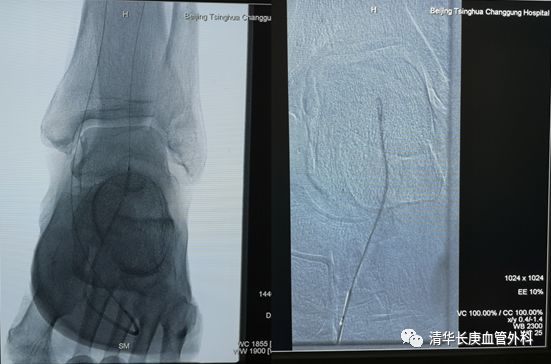

下肢动脉粥样硬化闭塞症、糖尿病足腔内治疗往往充满悬念,完全闭塞严重钙化病变的“遭遇战”极具挑战。张童副主任医师为大家演示了膝上、膝下不同部位的CTO病变突击战,风格迥异:一例胫前动脉CTO病变,通过胫后动脉Loop技术重建足背动脉,在此基础上“接力”逆穿足背末节趾间动脉起始段,方案应变坚决果断,思路出乎意料,入路精准稳定,博得满堂彩。

膝上动脉病例是一例股浅动脉粥样硬化闭塞,亮点一是通过病变的导丝导管技术秉承真腔通过理念,时长30秒!亮点二是目前备受关注的定向减容技术,操作行云流水,斑块悉数就擒。亮点三是药涂球囊扩张成形,无需支架置入,体内不留异物,延长通畅时间。